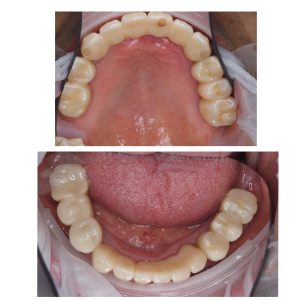

昨年フルマウスの方の定期検診

ネジの緩みもなく、値も良い

よく磨けている💪長持ちさせましょう!